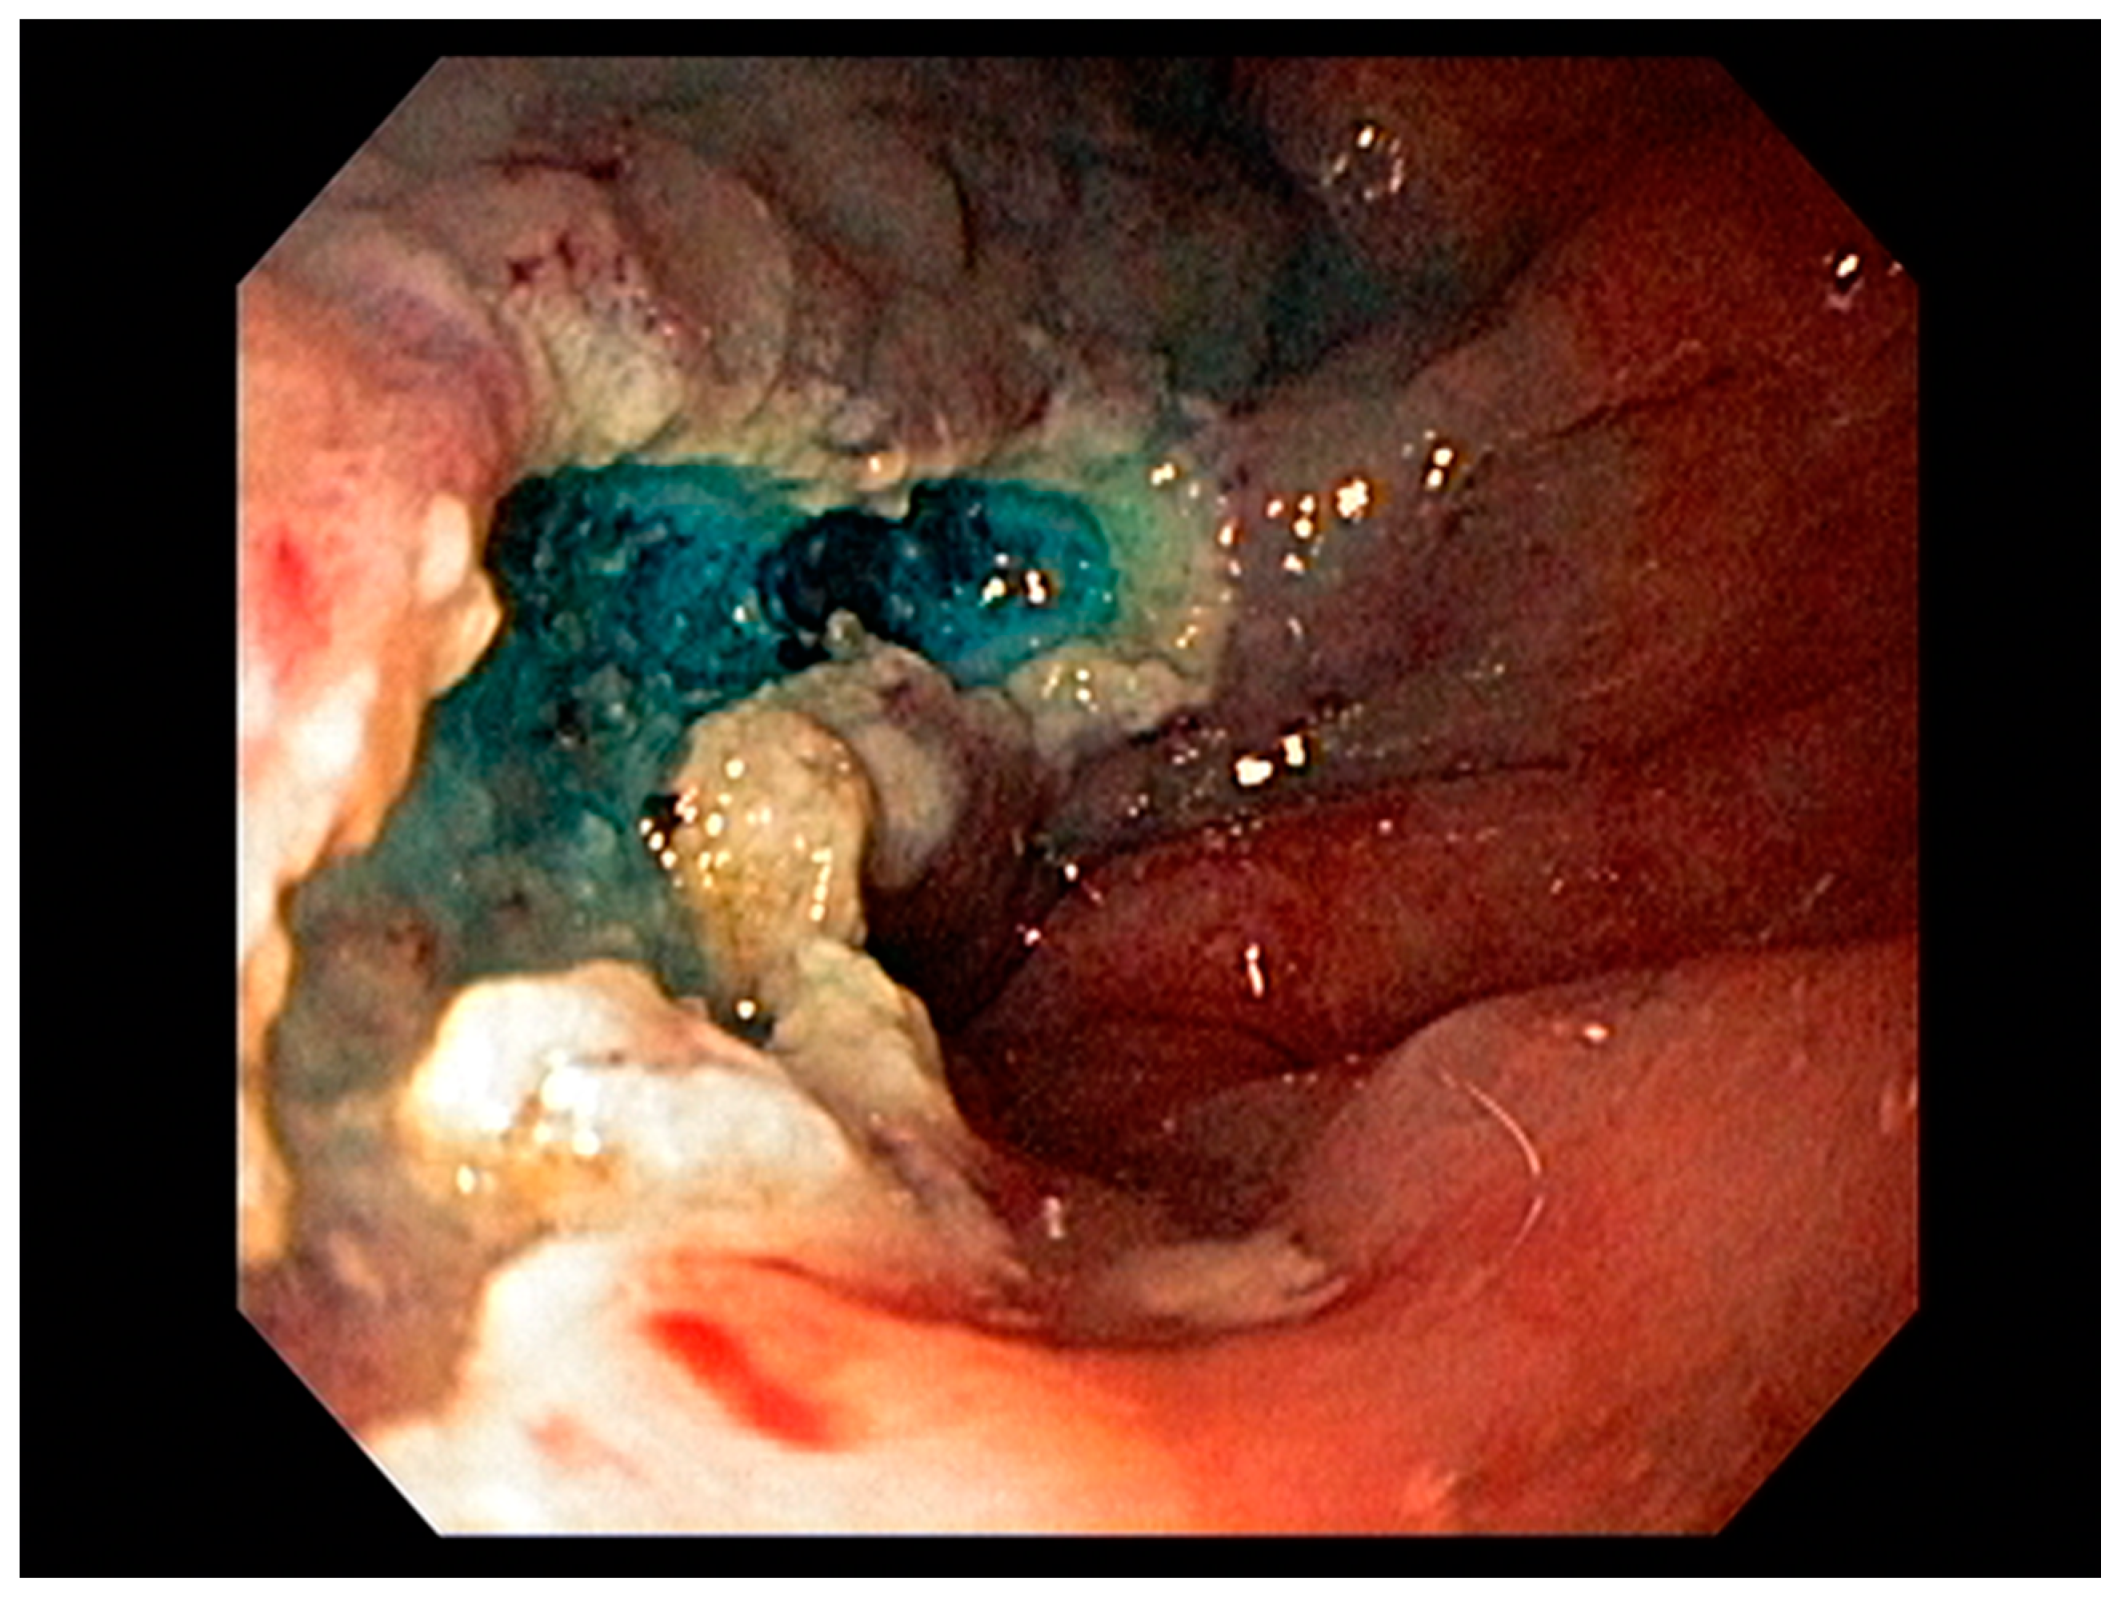

3.1. Endoscopic Therapeutic Options for Barrett’s Esophagus Associated Dysplasia

3.2. Endoscopic Resection Techniques for Early-Stage Esophageal Cancer (T1a and T1b)